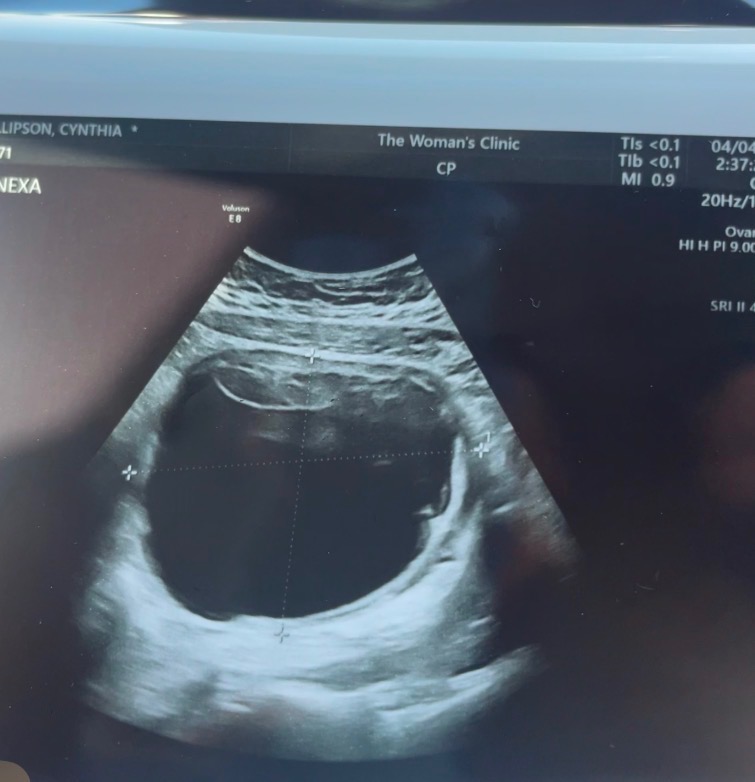

Hi, my name is Andrea Carter. I want to share my sister’s story. Cynthia Phillipson is 26 years old and has been with her husband, Blake Phillipson, for 8 years and married for 6 years. She has always dreamed of having children but unfortunate news after another, she has not yet had the chance. She has unfortunately been diagnosed with PCOS. Blake and Cynthia have been praying for a child for more than 5 years now. In May of 2024, just over a year ago, Cynthia had a laparoscopic surgery to drain a large cyst off of her uterus. The cyst was over 12cm long and 10cm wide. Her cycle did not come back after this surgery and after 5 months, she was left with the same agonizing back pain as before. By November of 2024, Cynthia was back at the doctor’s office again wondering if something had gone wrong. Her obgyn thought maybe something more was going on that they weren’t able to see on a sonogram and sent her to get an MRI. She was also referred her to a specialist oncologist obgyn. Cynthia went back and saw Dr. Daily on February 14, 2025 and got her results. She had a large tumor in her uterus which appeared to have some cancerous tissue. By March of 2025, she had an open abdominal myomectomy surgery to remove the new tumor and cyst. Cynthia was warned that if tests done on the samples showed clear signs of cancer, she would have a hysterectomy during the surgery. She had no idea the outcome of the surgery until she woke up and could think clearly. The results of the surgery listed the tumor as a “stump”, uterus in tact, 35 staples, and 6 weeks minimum bed rest to heal properly. Cynthia is still healing from this procedure. She was told to come back for a CT scan in 6 months and at 12 months she could start trying for a baby again! October of 2025 she had her CT and it shows she has a mass on her lung as well as the tumor seems to regrown in her uterus. Not long after she got a MRI to see more. On October 31st, Cynthia found out that the tumor had in fact come back, but this time in only 6 months. We all feared this outcome because unfortunately, she will have to be reopened for a hysterectomy. They will test the tumor to see if it’s cancerous or benign. It is such devastating news for her. Finding out news like that at only 26 years old has caused so much pain for her.